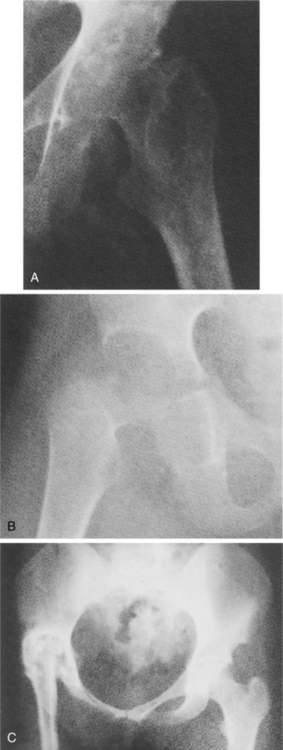

In the joint, if TB is diagnosed early when the infection is confined to the synovium, rest, medication, and joint protection may be adequate. In advanced disease with caseation, fibrosis, and scarring, the vascularity is reduced (Fig. 25-5), which makes medications less effective. Surgical excision or curettage of the affected areas may be necessary. In joints the granulomatous tissue acts to separate the articular cartilage from the underlying bone.

Figure 25-5 Tuberculous arthritis. A, Bony erosion of acetabulum and femoral head with joint space loss. There also is evidence of periarticular osteopenia. B, Similar findings to A but with further destruction of the femoral head and acetabulum. C, Advanced TB of the hip with superior displacement and ankylosis of the right hip joint. (From Yao D, Sartoris D: Musculoskeletal tuberculosis, Radiol Clin North Am 33:687, 1995.)